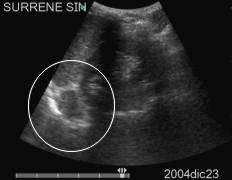

Data inserimento: 28/12/2004

Data esame: 23/12/2004

Strumento: Sonosite

Età paziente: M 64 anni

Neoformazioni surrenaliche bilaterali di maggiori dimensioni al surrene sinistro, asintomatiche.

Elaborazione digitale: Andrea Dini

In collaborazione: Dr. Davide Agostini, Dr.ssa Ornella Orsini